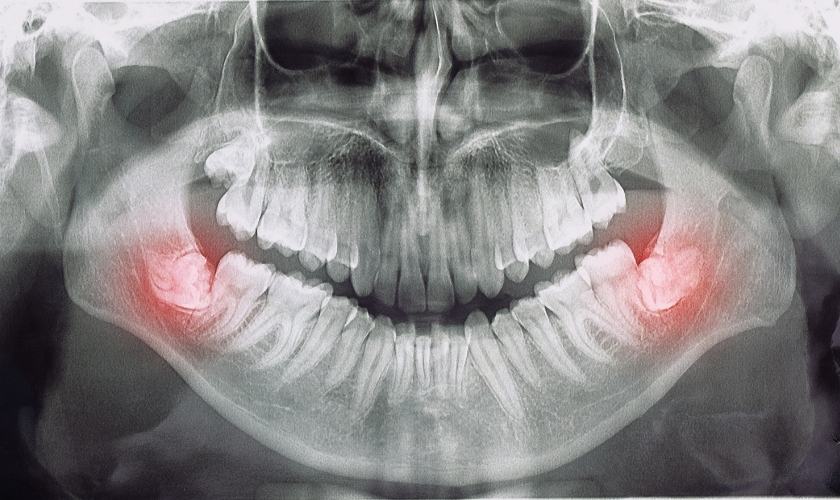

La aparición de las muelas del juicio puede provocar diversos problemas dentales. Debido a la falta de espacio en la mandíbula, las muelas del juicio pueden erupcionar parcial o completamente impactadas, es decir, que no pueden salir completamente de las encías.

Esto puede causar dolor, inflamación e infección. Además, las muelas del juicio también pueden ejercer presión sobre los dientes adyacentes, causando apiñamiento y desalineación dental.

Problemas comunes asociados con las muelas del juicio impactadas

Cuando las muelas del juicio no tienen suficiente espacio para salir, pueden quedar impactadas en la mandíbula o en las encías. Esto puede causar dolor, hinchazón, infecciones y daño a los dientes vecinos, lo que hace que la extracción sea necesaria en muchos casos. Las muelas del juicio impactadas también pueden causar la formación de quistes o tumores en el área afectada.